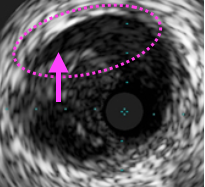

黒い太目の円状ラインがEEMで、

EEMの内側にある、目の粗いく映る組織がプラーク、

そしてプラークの内側で細かい粒がジャミジャミしている部分が血流、

プラークと血流の境界線が血管内膜だ!